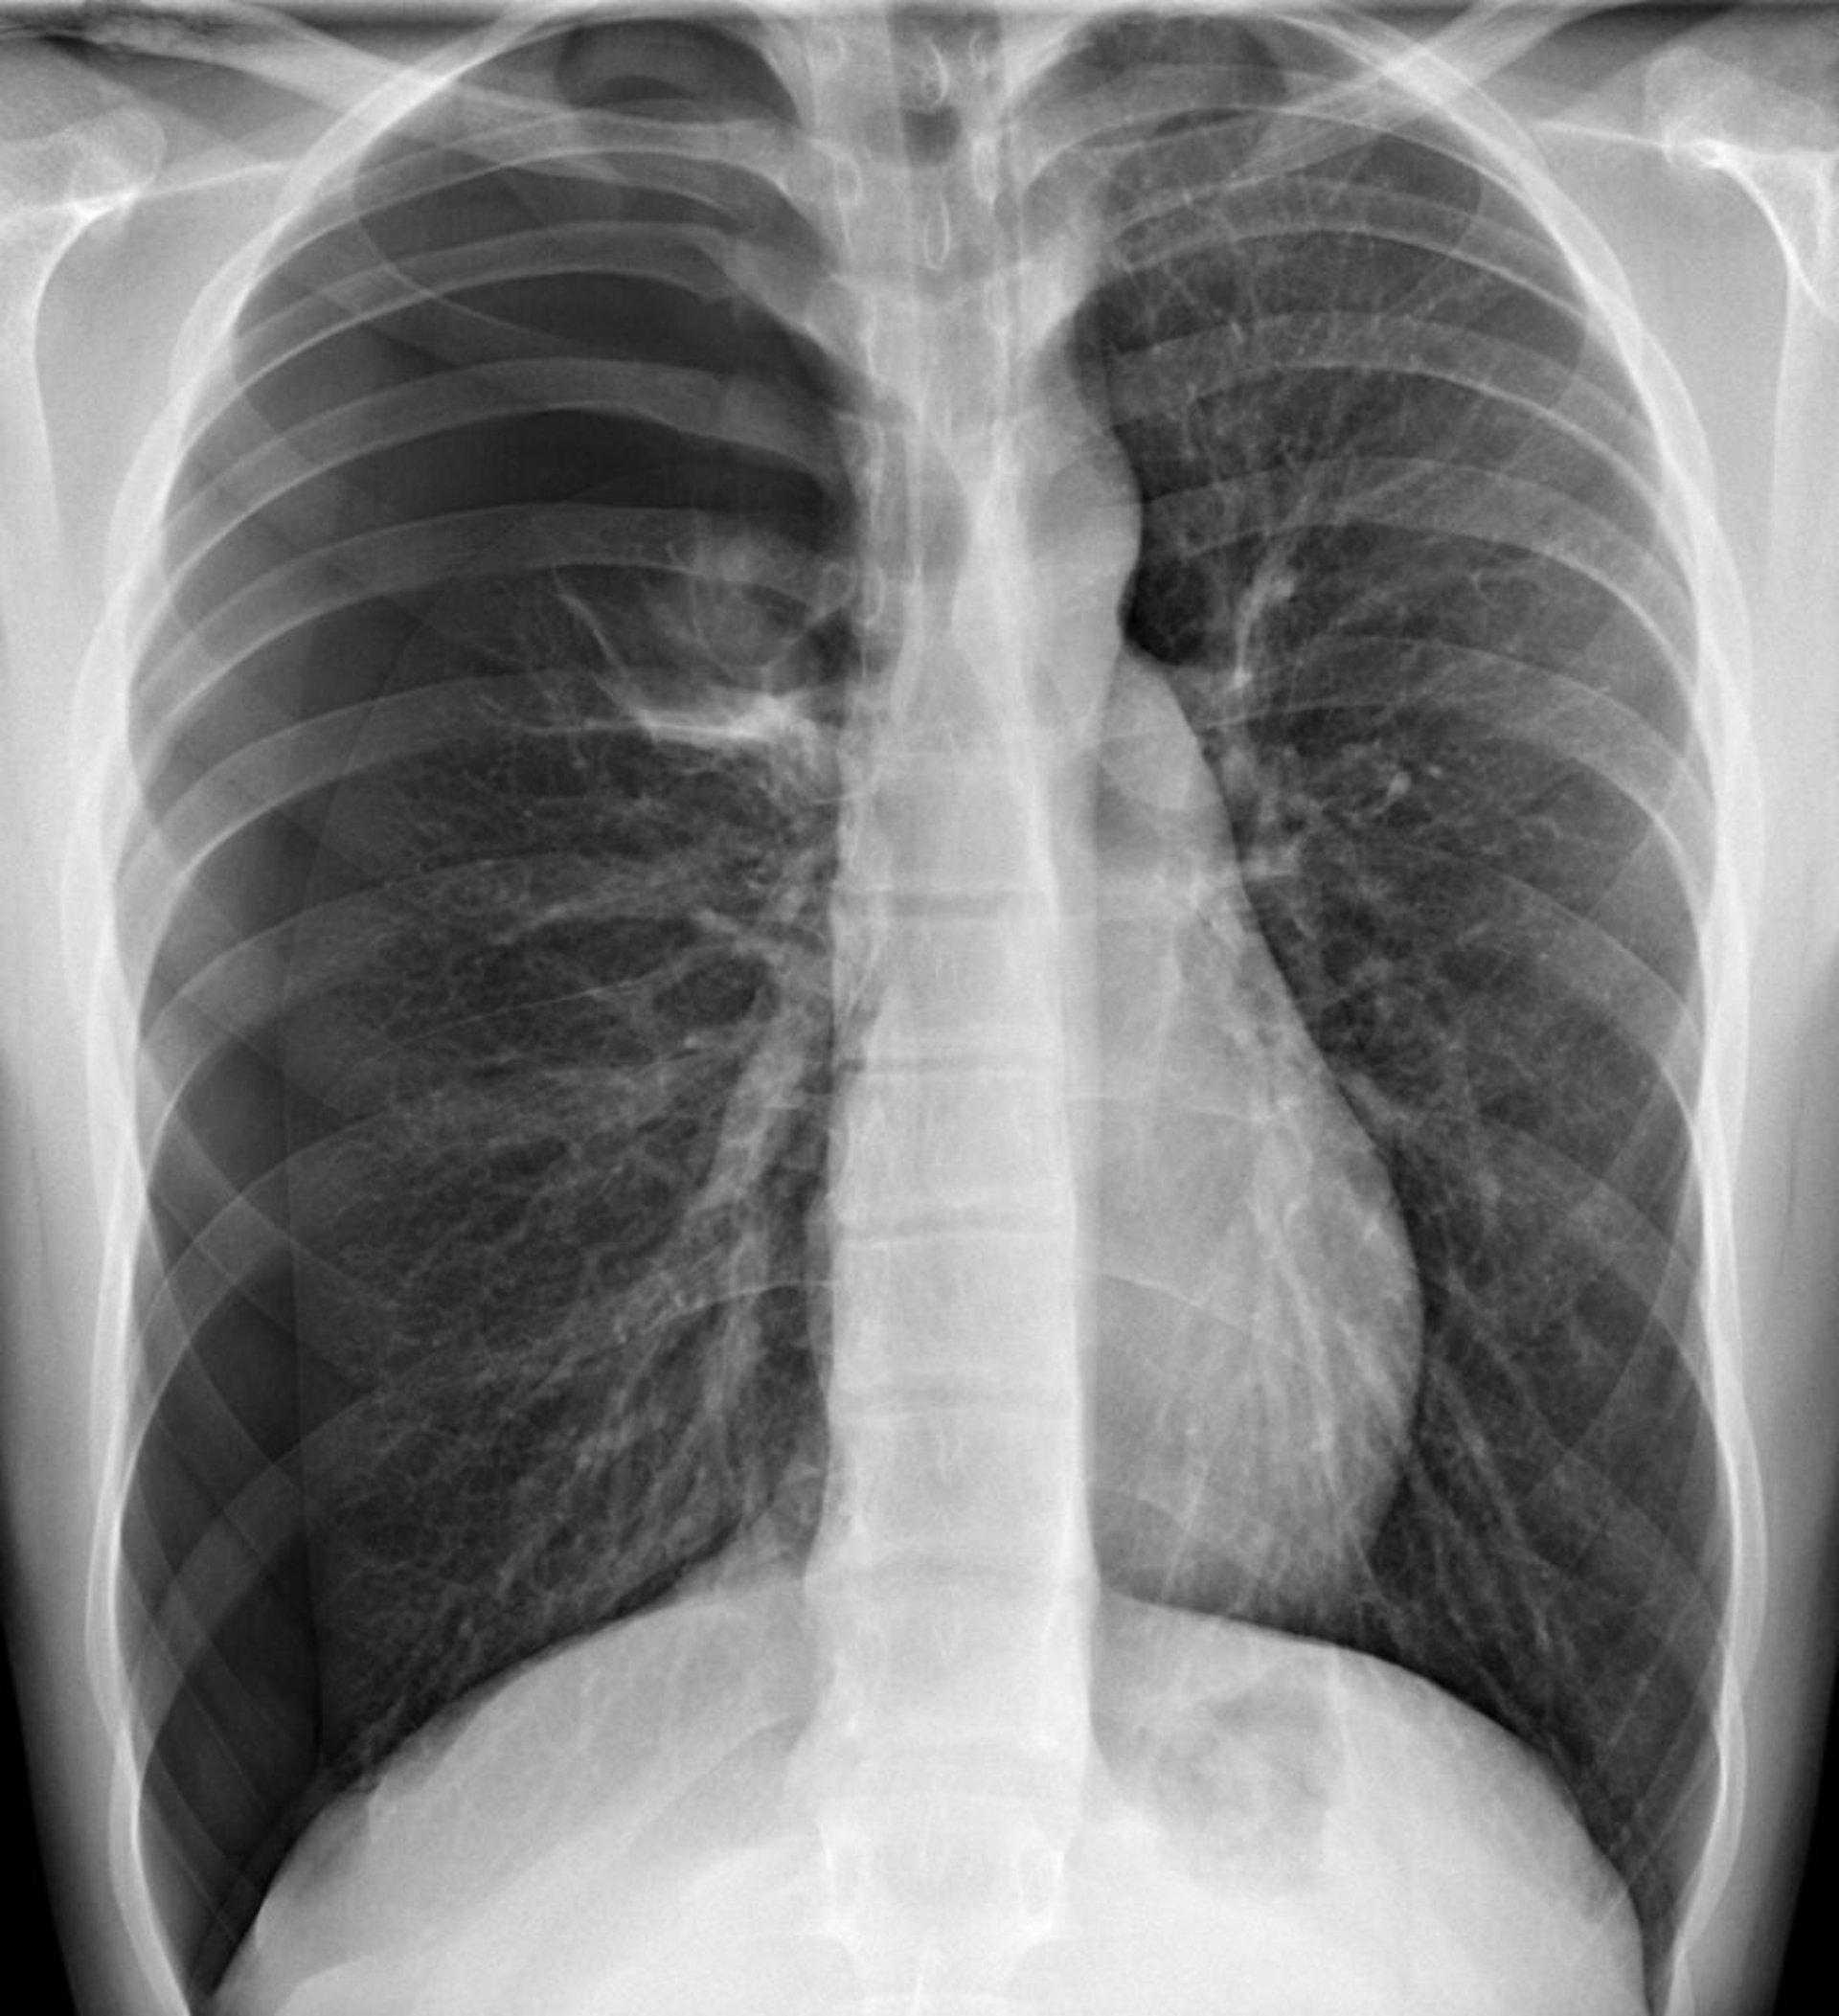

Spannungspneumothorax

Auf diesem Bild ist ein Pneumothorax im rechten Hemithorax zu sehen, wo in der Peripherie keine Lungenmarkierungen vorhanden sind. Eine Verschiebung des Herzens und des Mediastinums nach links kann physiologisch einen Spannungspneumothorax verursachen. Ein Spannungspneumothorax sollte jedoch klinisch diagnostiziert werden und nicht erst durch eine Röntgenaufnahme bestätigt werden.

DU CANE MEDICAL IMAGING LTD/SCIENCE PHOTO LIBRARY